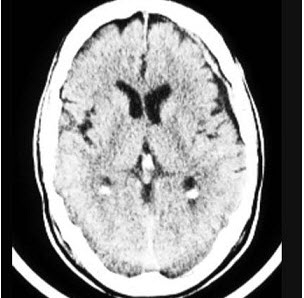

28、单项选择题

患者,女,65岁,进行性加重的近记忆力减退,缓慢行走,交谈能力减退,付错钱。CT表现如图

最可能的诊断是()

A.A1zheimer病

B.帕金森病

C.抑郁症

D.轻度认知障碍

E.多发性脑梗死